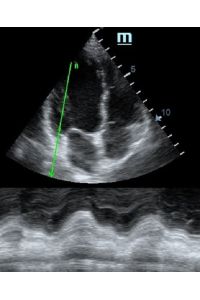

TAPSE - показатель амплитуды движения латеральной части кольца трикуспидального клапана, позволяет количественно и быстро оценить систолическую функцию правого желудочка, норма которого составляет более 17 мм. Главным условием является проведение линии М-режима параллельно стенке правого желудочка в апикальном четырех камерном сечении, что легко достигается при Free Xros.